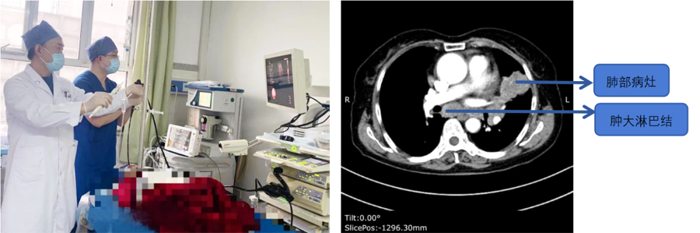

近日,我院呼吸與危重癥醫(yī)學(xué)科一病區(qū)在疼痛科及內(nèi)鏡中心的配合下,成功開展超聲支氣管鏡引導(dǎo)下經(jīng)支氣管針吸活檢術(shù)(EBUS-TBNA)。術(shù)中聯(lián)合應(yīng)用現(xiàn)場快速評價(ROSE),操作安全、高效、患者舒適,取材量可觀,均得到了快速確診。

病例1

患者,女,72歲,2月來“反復(fù)咳嗽、咳痰,偶咳白痰中帶血絲”,胸部CT提示“肺占位、肺炎”,收住院。完善胸部強(qiáng)化CT提示“左肺占位、肺炎、縱膈多發(fā)淋巴結(jié)腫大”,電子支氣管鏡檢查見左肺上葉支氣管血塊及壞死物阻塞,清除后見管腔通暢,刷檢DNA細(xì)胞學(xué)示“細(xì)胞退變明顯,建議進(jìn)一步檢查”。10月27日行CT引導(dǎo)下肺穿刺活檢,病理示“機(jī)化性肺炎”,給予抗感染及激素治療,患者癥狀好轉(zhuǎn)出院。半月前,患者復(fù)查肺CT發(fā)現(xiàn)病灶較前稍有增大,張強(qiáng)主任考慮患者癥狀雖有好轉(zhuǎn),但仍存在腫瘤性病變可能性。經(jīng)過討論及與患者家屬充分溝通后,決定實(shí)施支氣管內(nèi)超聲引導(dǎo)下針吸活檢術(shù)(EBUS-TBNA)+電子支氣管鏡檢查+現(xiàn)場快速評價(ROSE)技術(shù),以提高診斷陽性率。術(shù)中ROSE提示查找到可疑癌細(xì)胞,取材量較足分。最后病理檢查明確診斷為低分化肺腺癌,隨后進(jìn)行基因檢測,明確了治療方向。